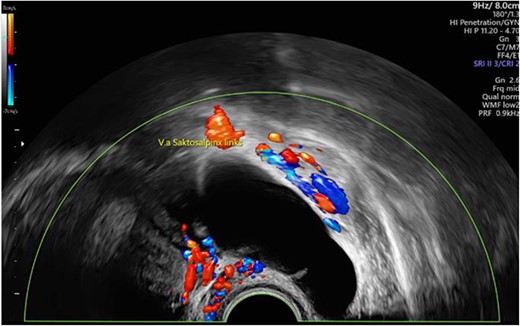

We report of a 29-year-old patient (G2/P1) who was referred in our department with secondary infertility and suspicion of hydrosalpinx for further diagnosis. The patient had no previous diseases, did not take medication regularly and had a regular menstrual cycle. The patient had undergone surgical laparoscopy with salpingotomy on the right side for extrauterine pregnancy. Preoperatively, there was the sonographic suspicion of hydrosalpinx on the left side (64 × 26 mm2, echo-poor with dorsal sound enhancement) and of a simple ovarian cyst of the left ovary (Fig. 1). Otherwise, sonography revealed unremarkable internal genitalia, no free fluid in the Douglas space. Hysteroscopy, chromopertubation, laparoscopy and cyst extirpation on the left and, if necessary, salpingectomy on the left were discussed with the patient.

Preoperative sonographic suspicion of hydrosalpinx on the left side (64 × 26 mm2, echo-poor with dorsal sound enhancement).